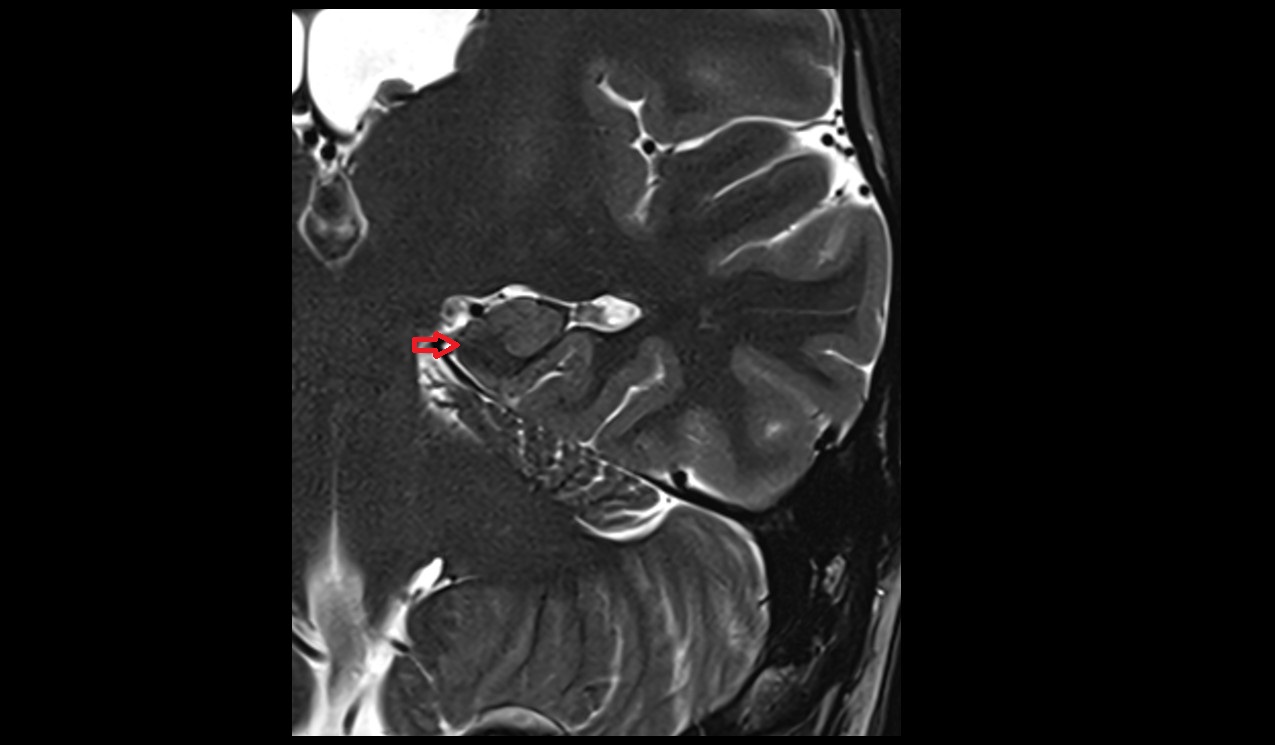

- Uterus

- Body of uterus

- Fundus of uterus

- Cervix of uterus

- Isthmus of uterus

- Vagina

- Fornix of the vagina

- Endometrium of uterus

- Myometrium of uterus

- Perimetrium of uterus

- Junctional zone of uterus